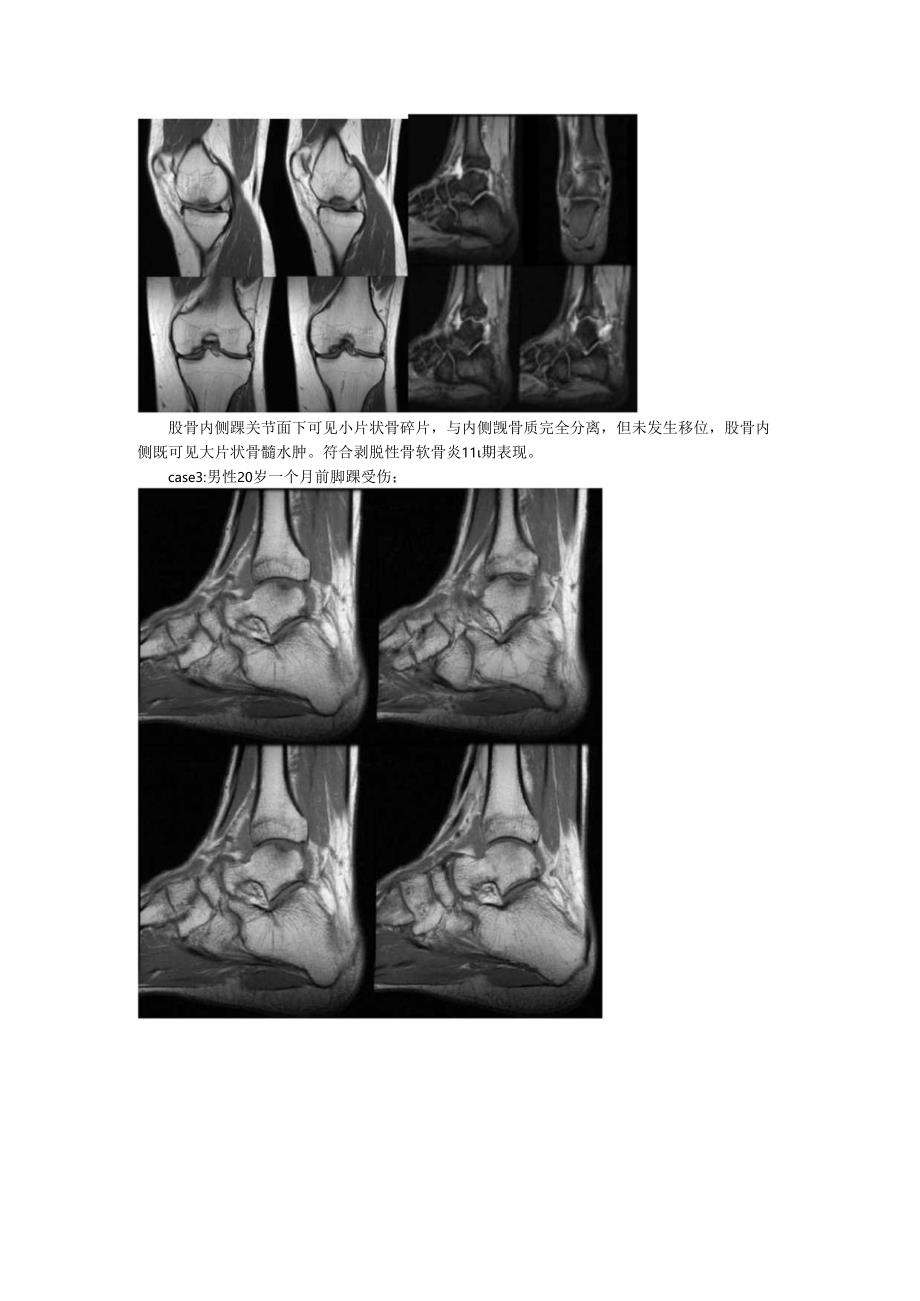

3、病变,部分早期病灶平片难以显示;CT扫描显示骨关节面下局部骨密度不均匀减低,局限性凹陷样缺损,边缘薄层硬化,病变处小块死骨,周围环绕一圈低密度;CT三维重建通过冠状面,横轴位对病变部位进行分析,显示病变的范围及死骨明显优于X射线;MRI扫描显示关节软骨下剥脱的死骨,表现为病变处骨髓信号异常,TlWI稍低信号,T2WI为稍高信号,骨髓水肿在T2WI呈高信号,在STIRT2WI上尤其明显。easel:男性32岁膝关节疼痛不适入院就诊股骨内侧黑软骨面下骨质可见大片状骨髓水肿,软骨面下可见小片状长Tl、短T2信号,符合剥脱性骨软骨炎II期影像表现。另内侧半月板后角向外膨出,其内可见片状高信号。case

4、2:男性26岁活动后膝关节疼痛不适数月余,现如今疼痛加剧就诊;股骨内侧吸关节面卜.可见线状低密度影,边缘可见硬化边;股骨内侧踝关节面下可见小片状骨碎片,与内侧觊骨质完全分离,但未发生移位,股骨内侧既可见大片状骨髓水肿。符合剥脱性骨软骨炎11期表现。case3:男性20岁一个月前脚踝受伤;距骨后外侧骨软骨骨折;骨碎片分离并上翻转,胫骨远端和距骨骨髓水肿。红色箭头所指处为软骨碎片移位股骨踝关节面下可见表面缺损,累及其外侧表面,没有看到明显的骨碎片,考虑IV晚期。鉴别诊断剥脱性骨软骨炎主要应与骨坏死及结核鉴别;骨坏死骨密度增高,且体积变小;关节结核骨质破坏以关节面的边缘部为主,除非有继发感染存在,一